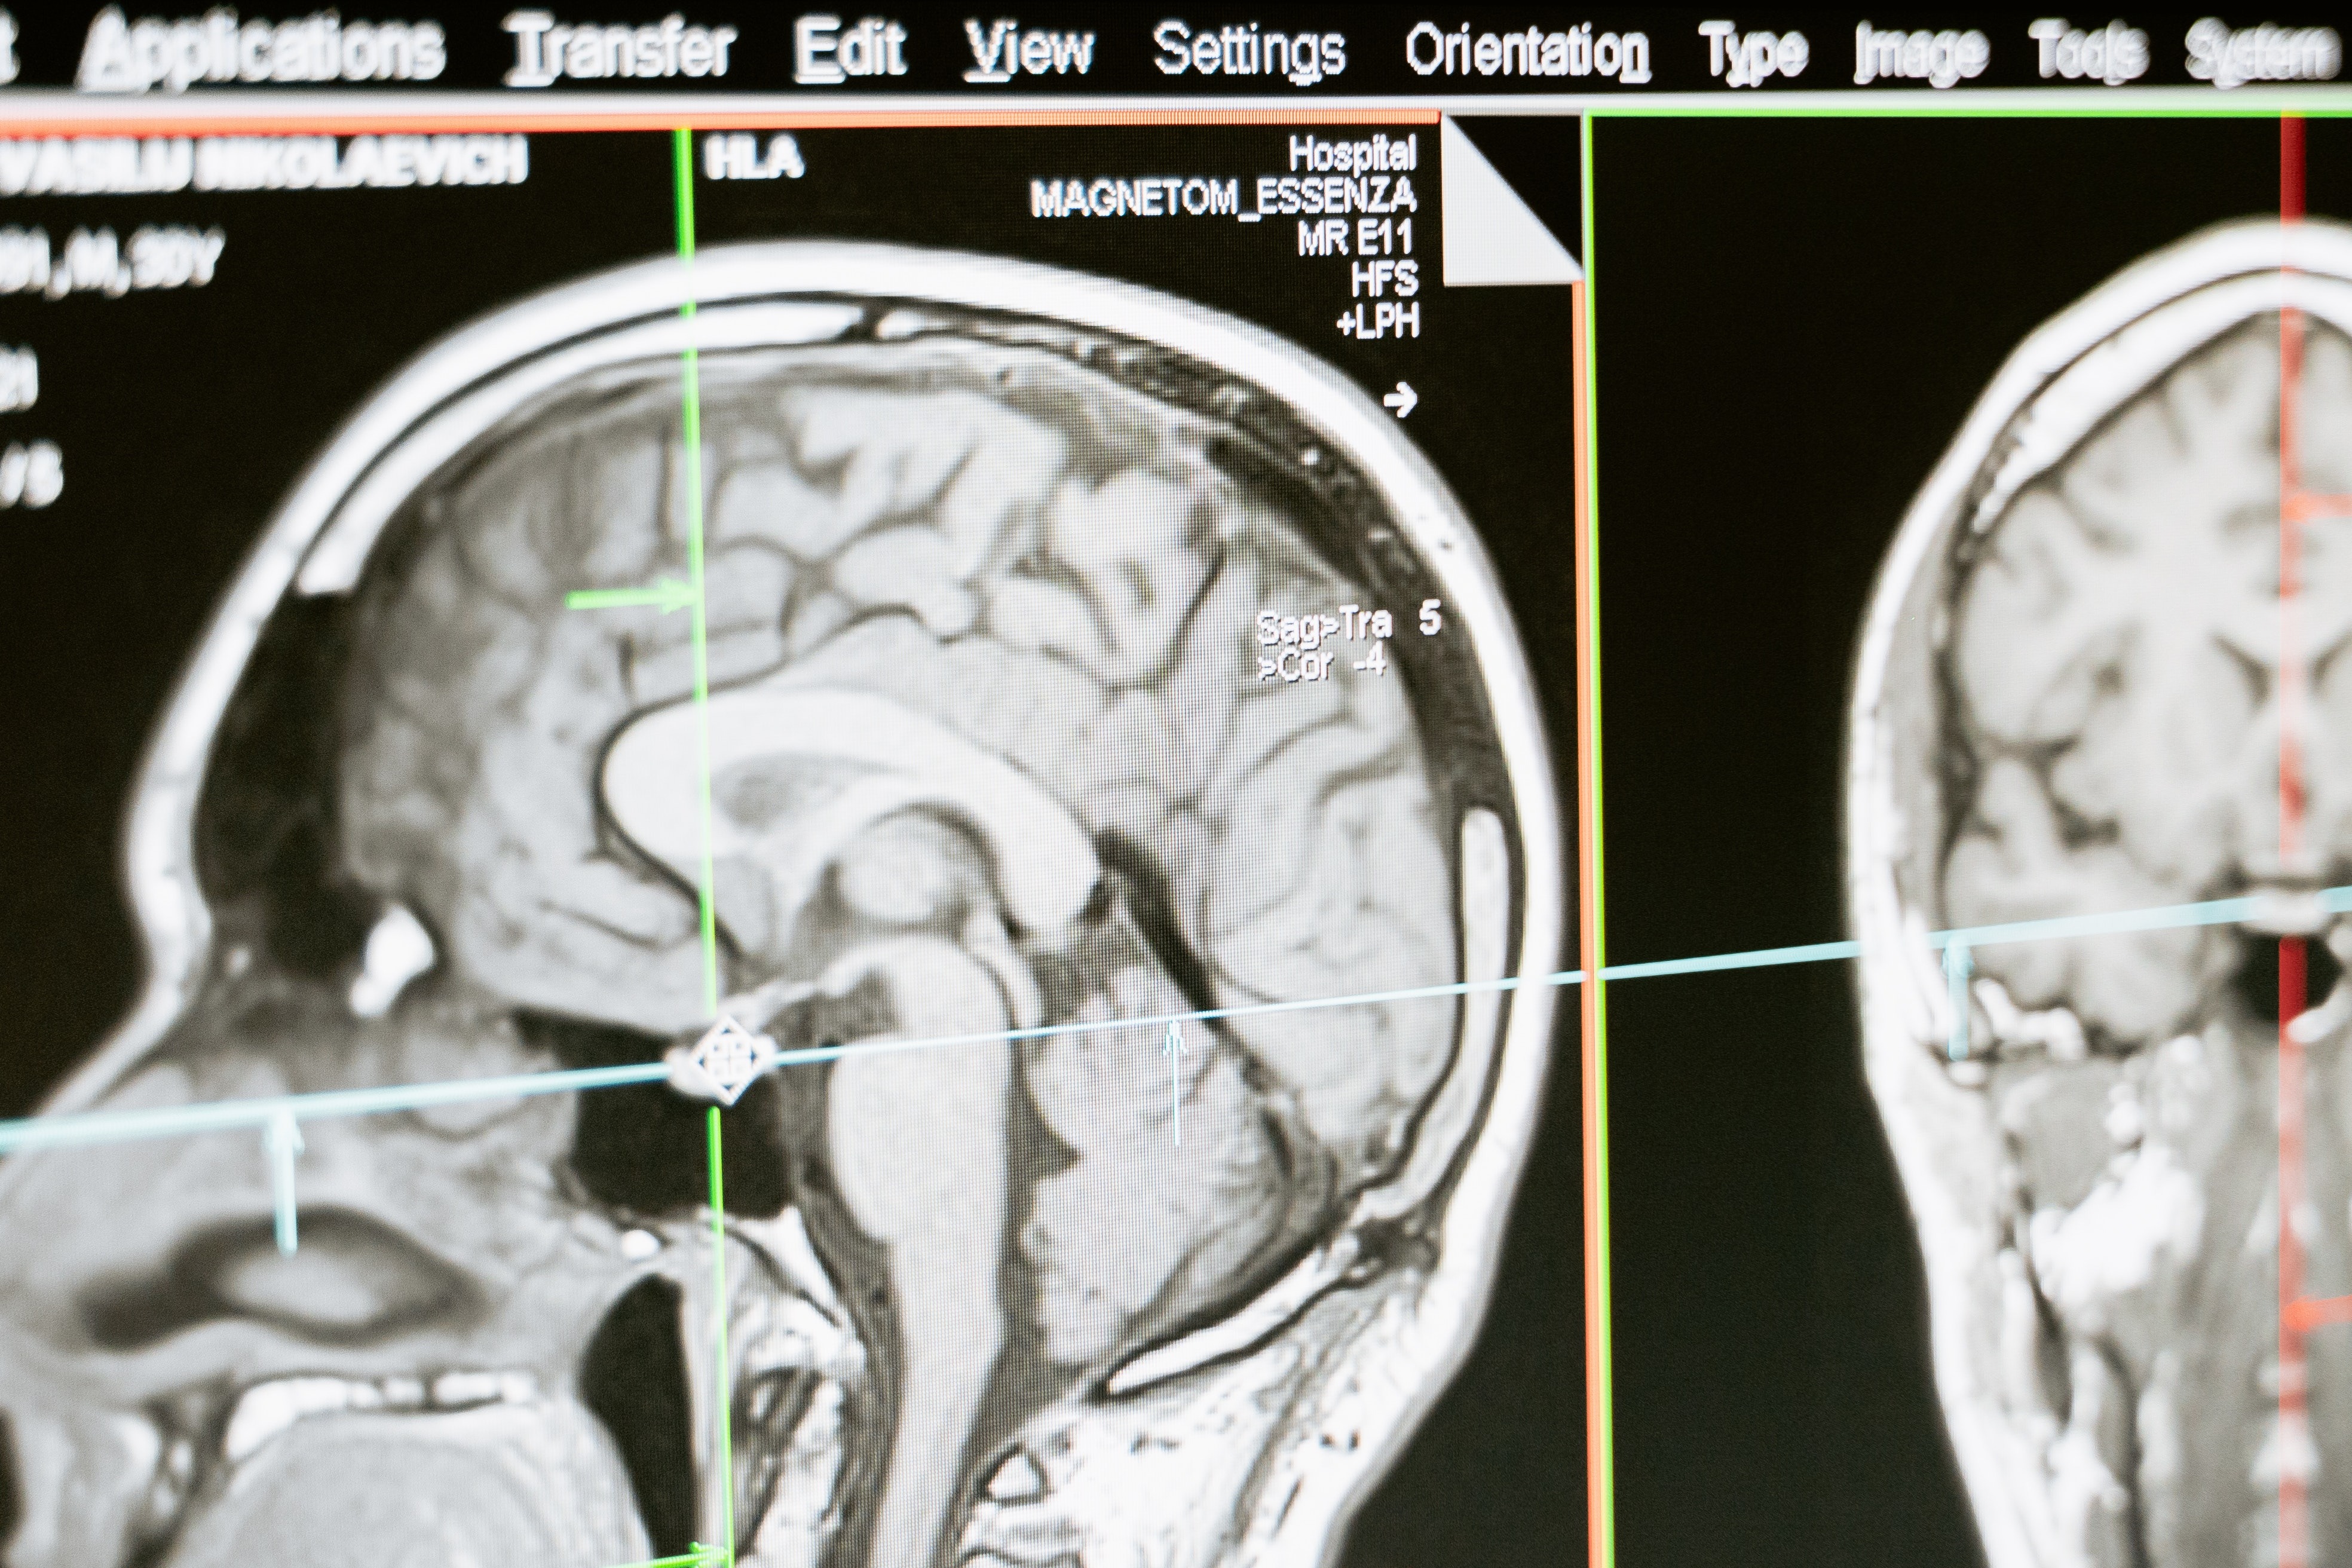

Brain Tumor Detection Using Deep Learning

Achieved 91% classification accuracy on MRI brain scan validation datasets by building and training a CNN model using TensorFlow and Keras. Reduced false positives by 20% through image preprocessing and data augmentation techniques such as rotation and flipping.